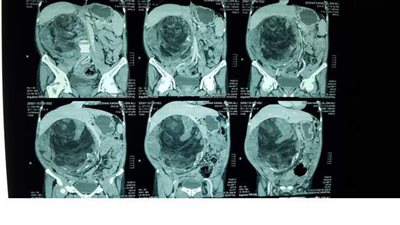

أجرى فريق جراحى بجامعة المنصورة عملية استئصال ورم بحجم كبير ضاغط على جميع الأجهزة الداخلية